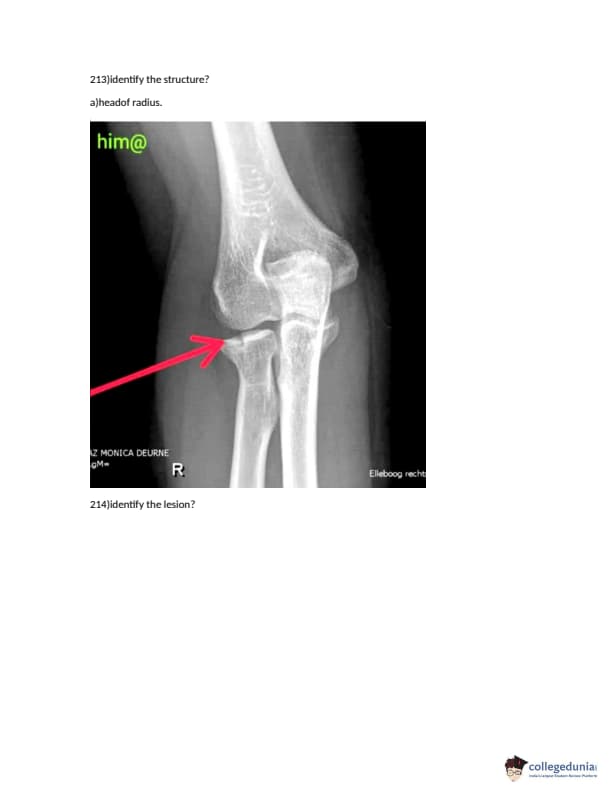

FMGE 2018 Question paper with answer key pdf conducted on December 14, 2018 is available for download. The exam was successfully organized by National Board of Examinations (NBE). The question paper comprised a total of 226 questions.